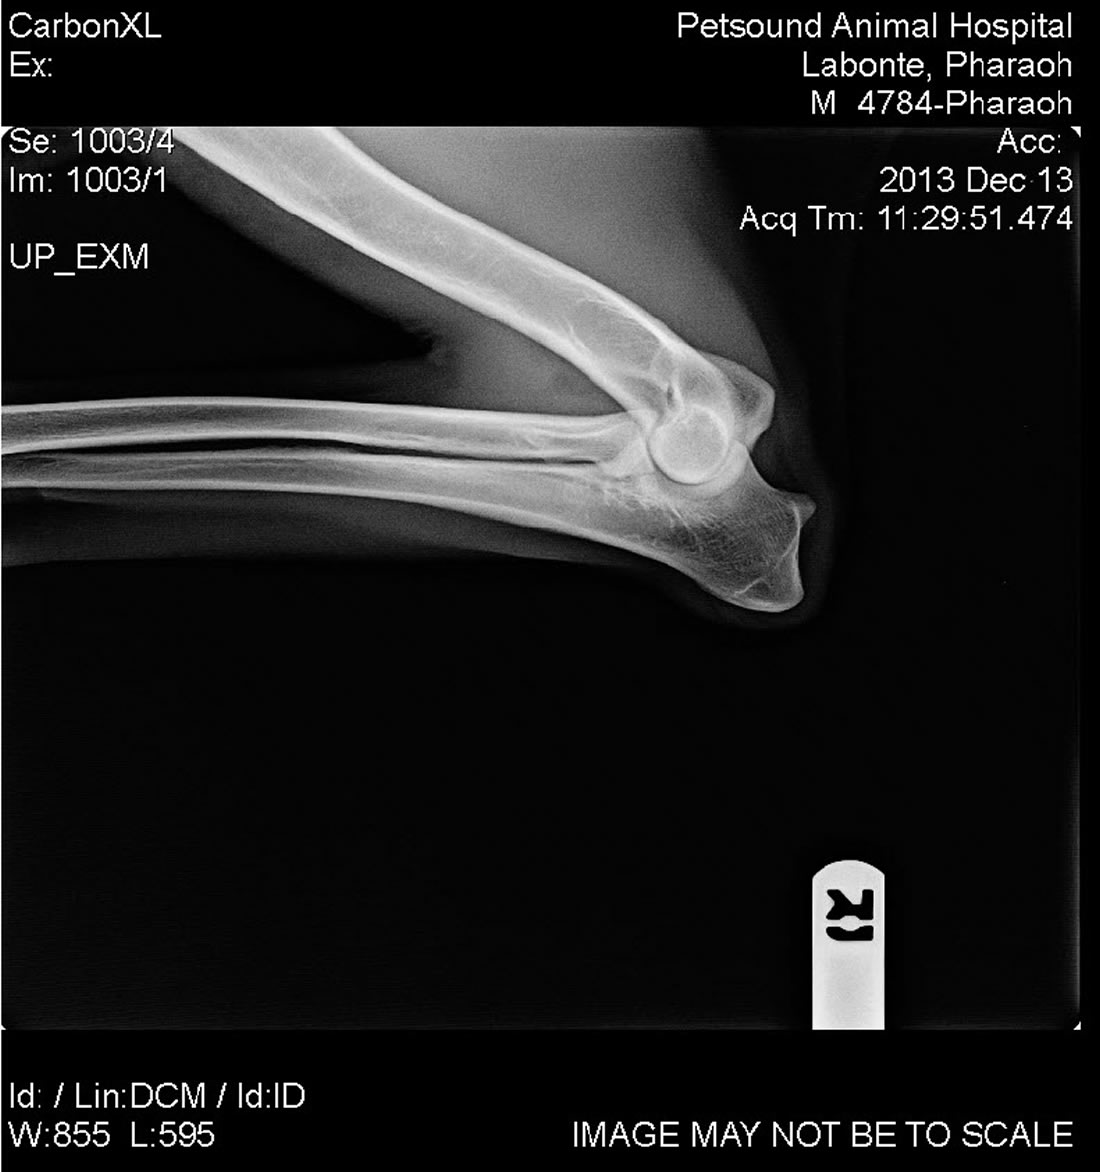

Labonte's Pharaoh - OFA Excellent

Labonte's Pharaoh - OFA Excellent is an extreme prey driven dog and is very fast with a 37mph escape. His hips have the rare OFA rating of Excellent. He is black with a very nice red color and a strong European structure. Pharoah's pedigree is nothing short of awesome. With dogs like Fero, Quinto, Orry and lines like Karthago, Antverpa, Tiekerhook, Korbelbach giving her a very well rounded foundation and strong genes for breeding.